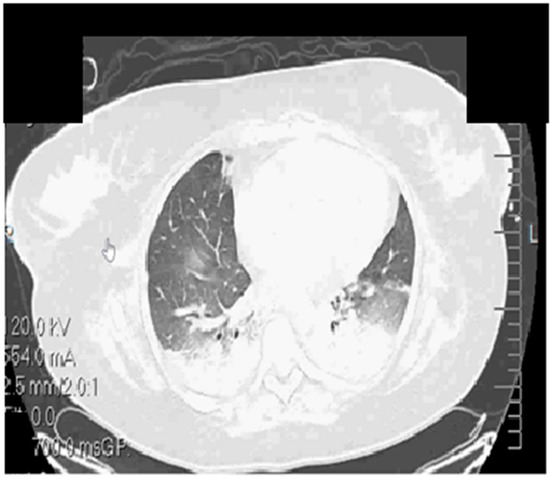

The initial CT Thorax scan identified multiple bilateral pulmonary infiltrates (Figure 1).

Figure 1. Native thorax CT at admission.